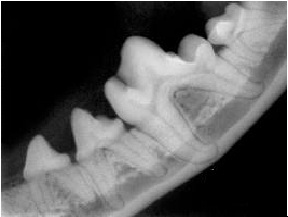

Dog and Cat Normal Dental X-Rays

X-Rays on Left -- Tooth supporting bone is normal in appearance